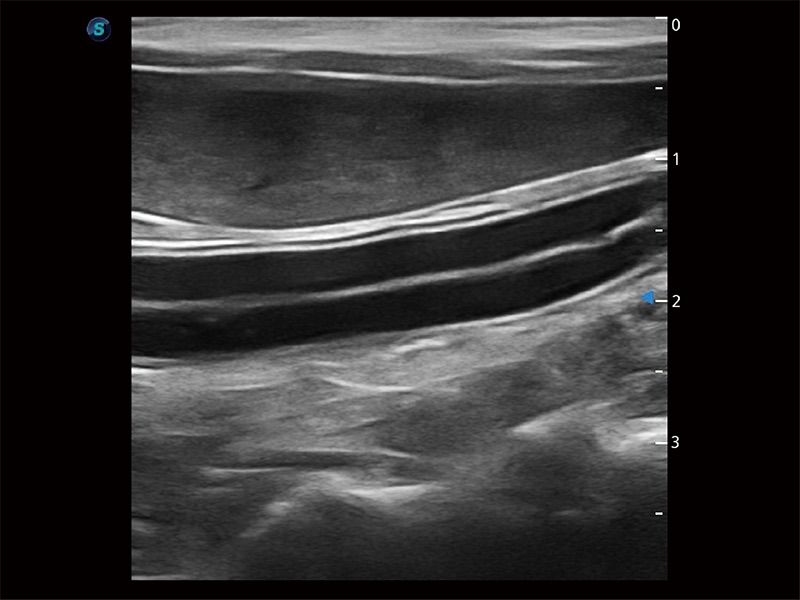

为精细结构及组织边缘提供高清晰度的图像和更大的成像视野。帮助减轻医生的用眼疲劳,快速精准获得测量的数据。

操作简便,无需高频度外力作用即可真实反映组织的形变,快速评估肿瘤良恶性。